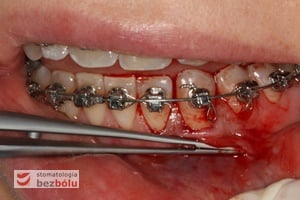

Recesje dzielimy na cztery klasy, w zależności od możliwości całkowitego pokrycia (wg Millera)

- klasa I recesje nie przekraczające linii śluzówkowo-dziąsłowej, przy których nie występuje ubytek tkanek w przestrzeniach międzyzębowych

- klasa II recesje sięgające do lub przekraczające linię śluzówkowo-dziąsłową, bez ubytku tkanek w przestrzeniach międzyzębowych

- klasa III recesje przekraczające linię śluzówkowo-dziąsłową, wraz z ubytkiem tkanek miękkich lub kości w przestrzeniach międzyzębowych

- klasa IV recesje przekraczają linię śluzówkowo-dziąsłową, a dodatkowo powikłane są rozległym zniszczeniem tkanek

W przypadku klas I i II można spodziewać się całkowitego pokrycia recesji, w klasie III częściowego, natomiast w IV klasie rokowanie pokrycia częściowego jest niepewne. Dlatego tak istotna jest wczesna i trafna diagnostyka recesji.